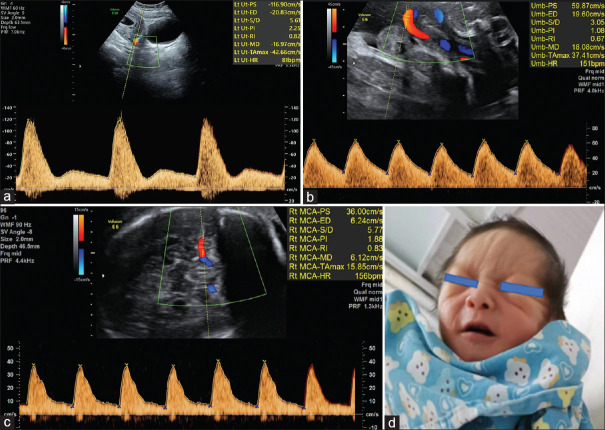

A Case of Mandibuloacral Dysplasia Progeroid Syndrome Presented as In Utero Growth Restriction.

以子宫内生长受限为表现的下颌肢发育不良类早衰综合征1例。